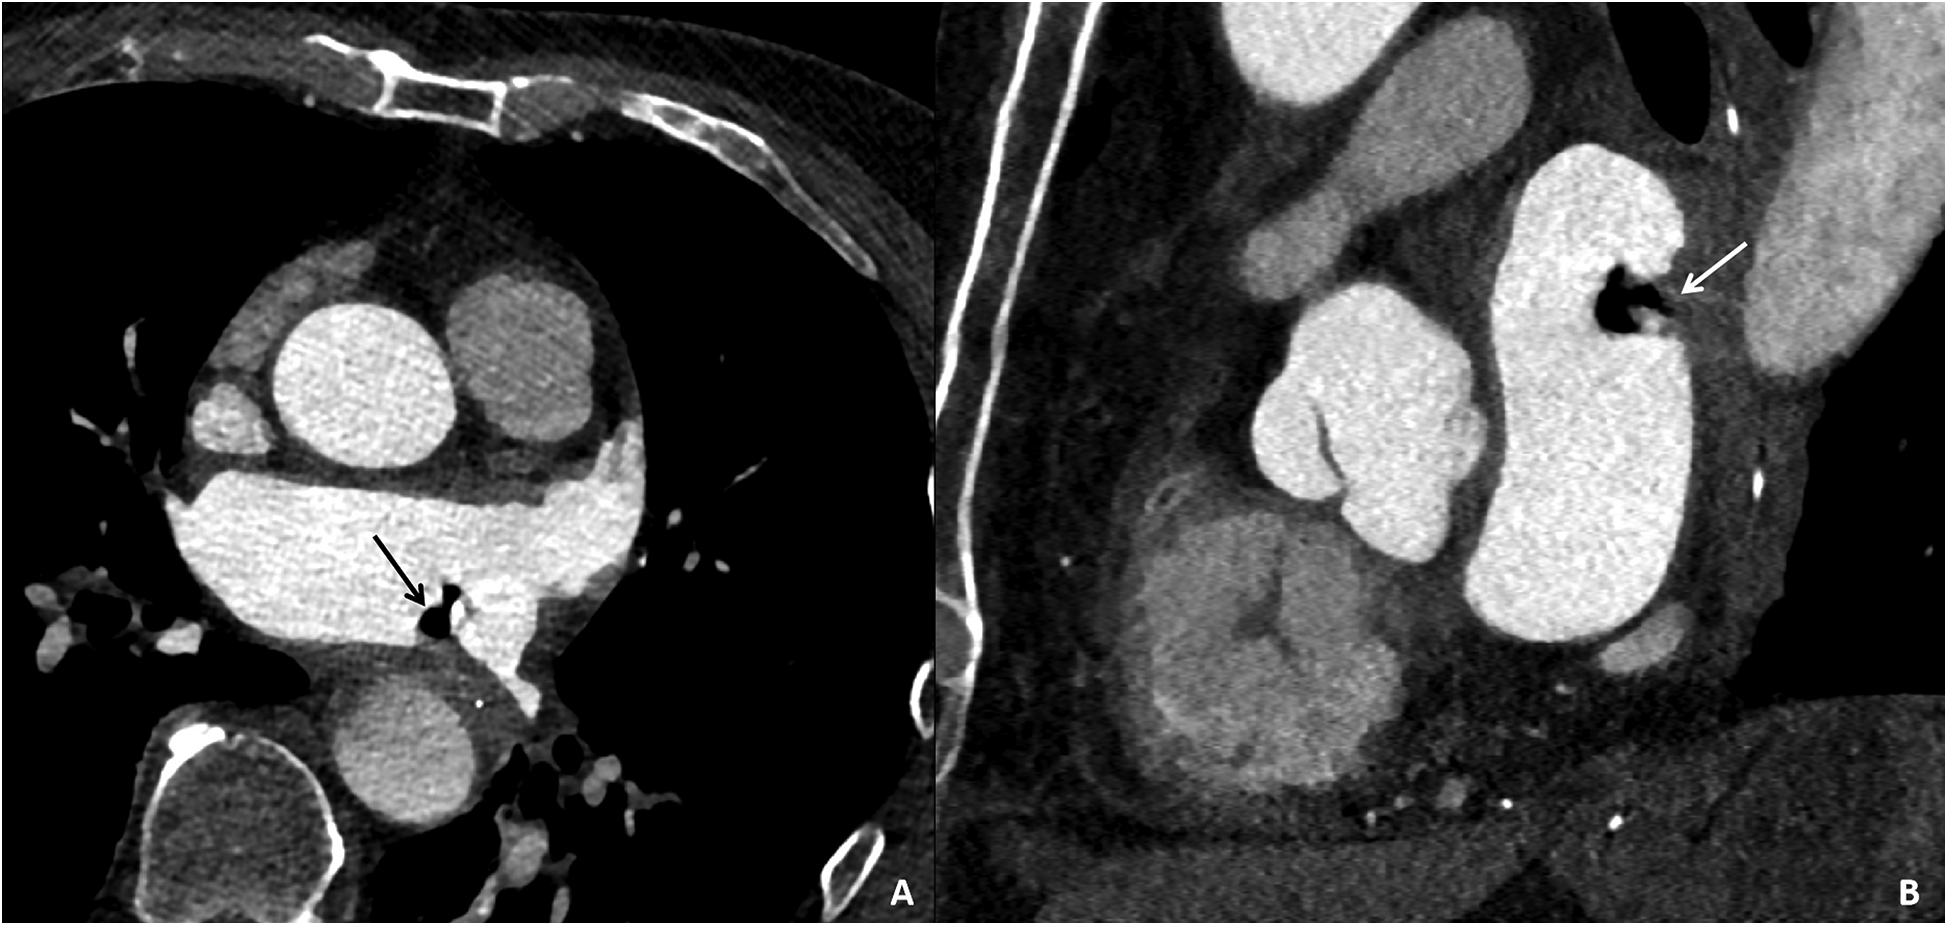

On the third day, during ward rounds, the patient was sedated with a pulse rate of 144 beats per min and a blood pressure of 78/69 mmHg. Further analysis of the patient's history revealed poor cardiac function and a critical condition. Review of the initial emergency CT scan indicated a small amount of air accumulation in the left atrial region, coupled with the recent history of radiofrequency ablation for atrial fibrillation, raising suspicion of an atrioesophageal fistula (AEF). Subsequent repeat cardiac CTA demonstrated a distinct radiolucent area within the left atrium, confirming the presence of air (Figure 4). Following multidisciplinary consultation, the patient was diagnosed with AEF, concurrent with acute myocardial infarction and cerebral infarction, likely due to air embolism. The treatment team informed the family about the patient's grave condition and, after deliberation, decided on conservative management with close and continuous monitoring of the patient's clinical status.

Figure 4

Cardiac CTA images of the patient taken on the third day of hospital admission. Contrast-enhanced CT images in the axial plane (A) and sagittal plane (B) reveal gas accumulation in the left atrial region, swelling of the adjacent esophageal wall, and obliteration of the fat planes surrounding the esophagus, confirming the presence of an esophago-left atrial fistula.